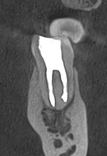

После неудачного лечения каналов в другой клинике у пациентки воспалился зуб внизу слева. Он болел и был под угрозой удаления — нужно было действовать быстро.

Лечение

Мы аккуратно перелечили корневые каналы с помощью микроскопа. Это позволило полностью очистить зуб и дать кости шанс восстановиться.